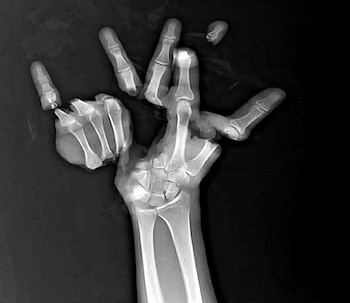

Urzúa Venegas subrayó que los artefactos pirotécnicos representan un alto riesgo, ya que no son juguetes y pueden ocasionar incendios tanto en el lugar donde se utilizan como a distancia. Además, señaló que estos productos son una de las principales causas de accidentes graves en menores de edad, entre ellos quemaduras, mutilaciones y amputaciones, por lo que reiteró el llamado a la población a evitar su uso.